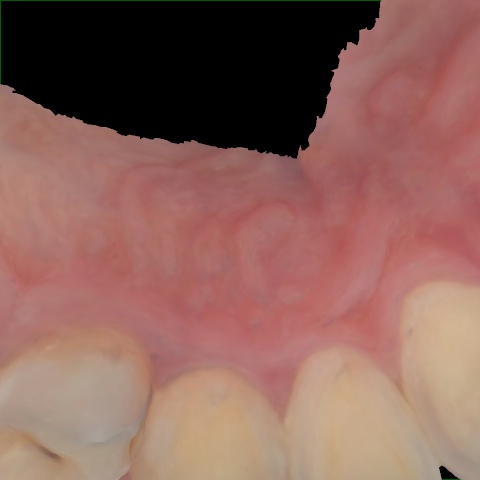

NHD39990

Annotated as "Good"

Original Image Rendering Image